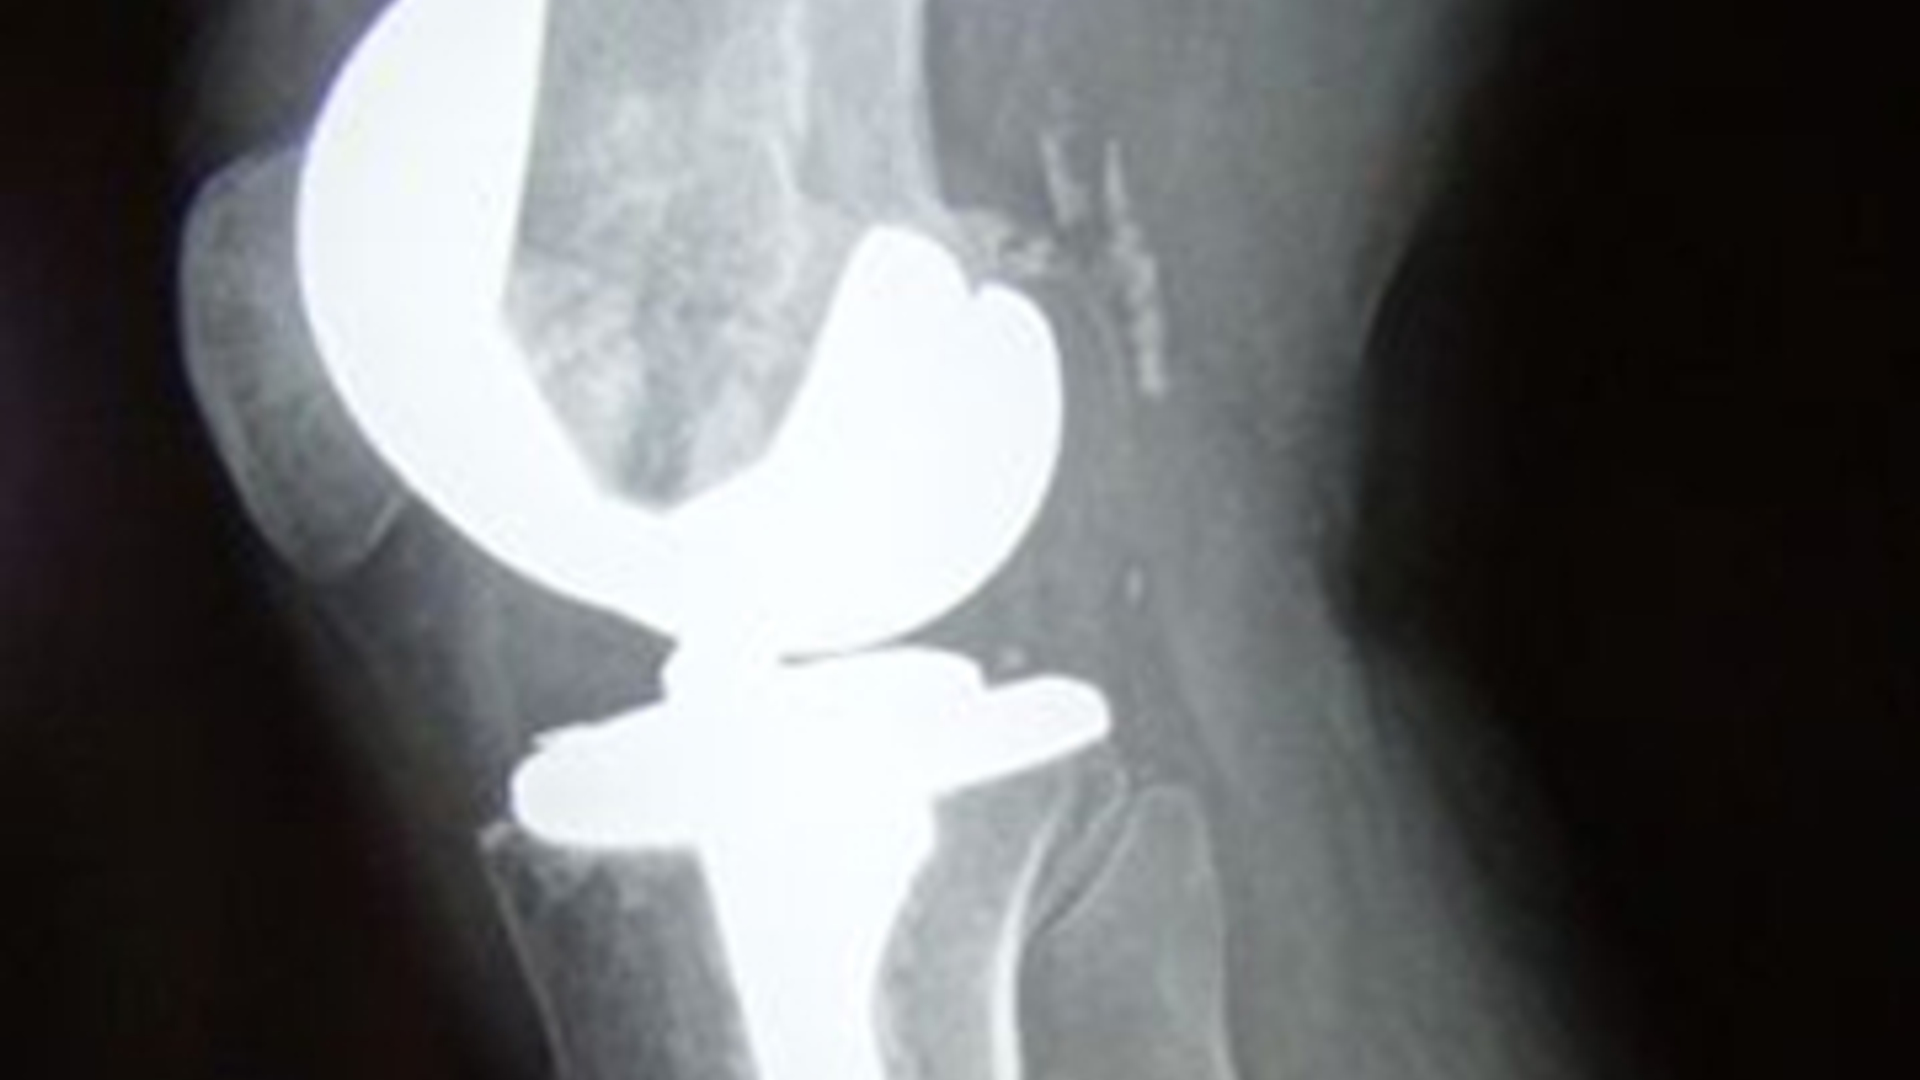

Er moet een keurmerk komen voor protheses en implantaten. Een onafhankelijk instituut moet deze producten van de orthopedische industrie wetenschappelijk testen op eventuele bijwerkingen alvorens zo'n keurmerk af te geven.

Volgens Öner en andere orthopeden schiet de controle op kunstlichaamsdelen in Nederland op dit moment ernstig tekort. Zo is de zogenoemde sportheup, een metalen vervanger voor een versleten heupgewricht, veel te haastig in Nederland ingevoerd. Nu blijkt dat de prothese ijzerslijpsel loslaat, wat bij enkele patiënten voor een tumor heeft gezorgd, stelt de Utrechtse orthopeed.

Zijn collega Rudolf Poolman van het Onze Lieve Vrouwe Gasthuis in Amsterdam zegt dat zes van de elf orthopedische bedrijven in Nederland geen inzicht willen geven in eventuele testen die met hun producten zijn gedaan. Hij overweegt een internetpagina te openen, waarop patiënten kunnen zien welke protheses en implantaten er in Nederlandse ziekenhuizen worden gebruikt en wat daarvan de resultaten en eventuele bijwerkingen zijn.

In Nederland werken ongeveer vijfhonderd orthopeden, die gezamenlijk duizenden patiënten per jaar zien. Vooral het aantal mensen dat een nieuwe knie of heup moet hebben neemt snel toe door de vergrijzing.